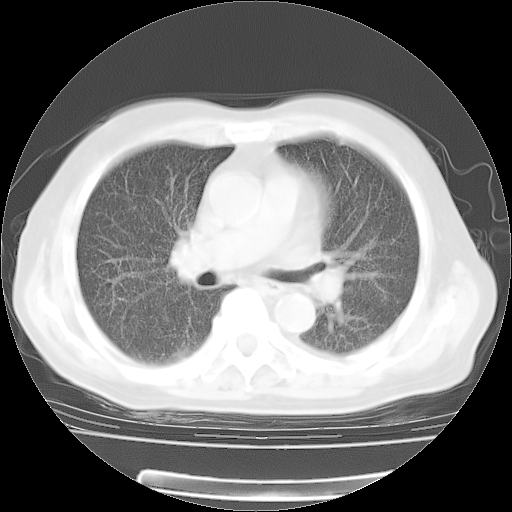

4月28日肺部CT